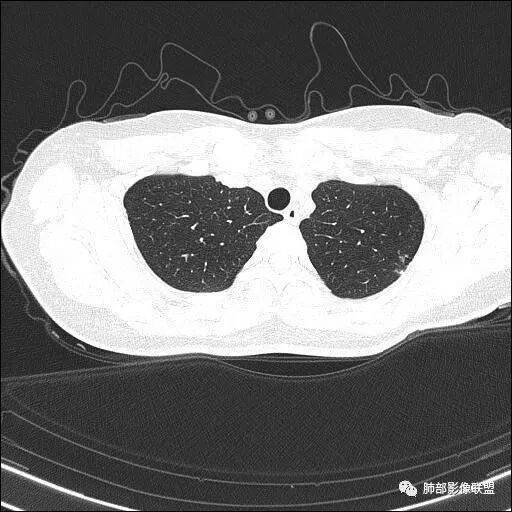

【每日晨读】双肺上叶多发薄壁空洞

1.年轻女性,体检发现肺部病灶

血常规正常

2.双肺多发薄壁空洞影、条索影及结节影,边界较清楚,密度偏高不柔和,散乱,但有成簇倾向或堆积感,胸膜下分布为主,双肺上叶分布为主。

3.空洞相当不规则,缺乏张力,未见血管穿行,未见壁结节,未见液平。

4.双肺门及纵隔未见肿大淋巴结。未见胸腔积液。